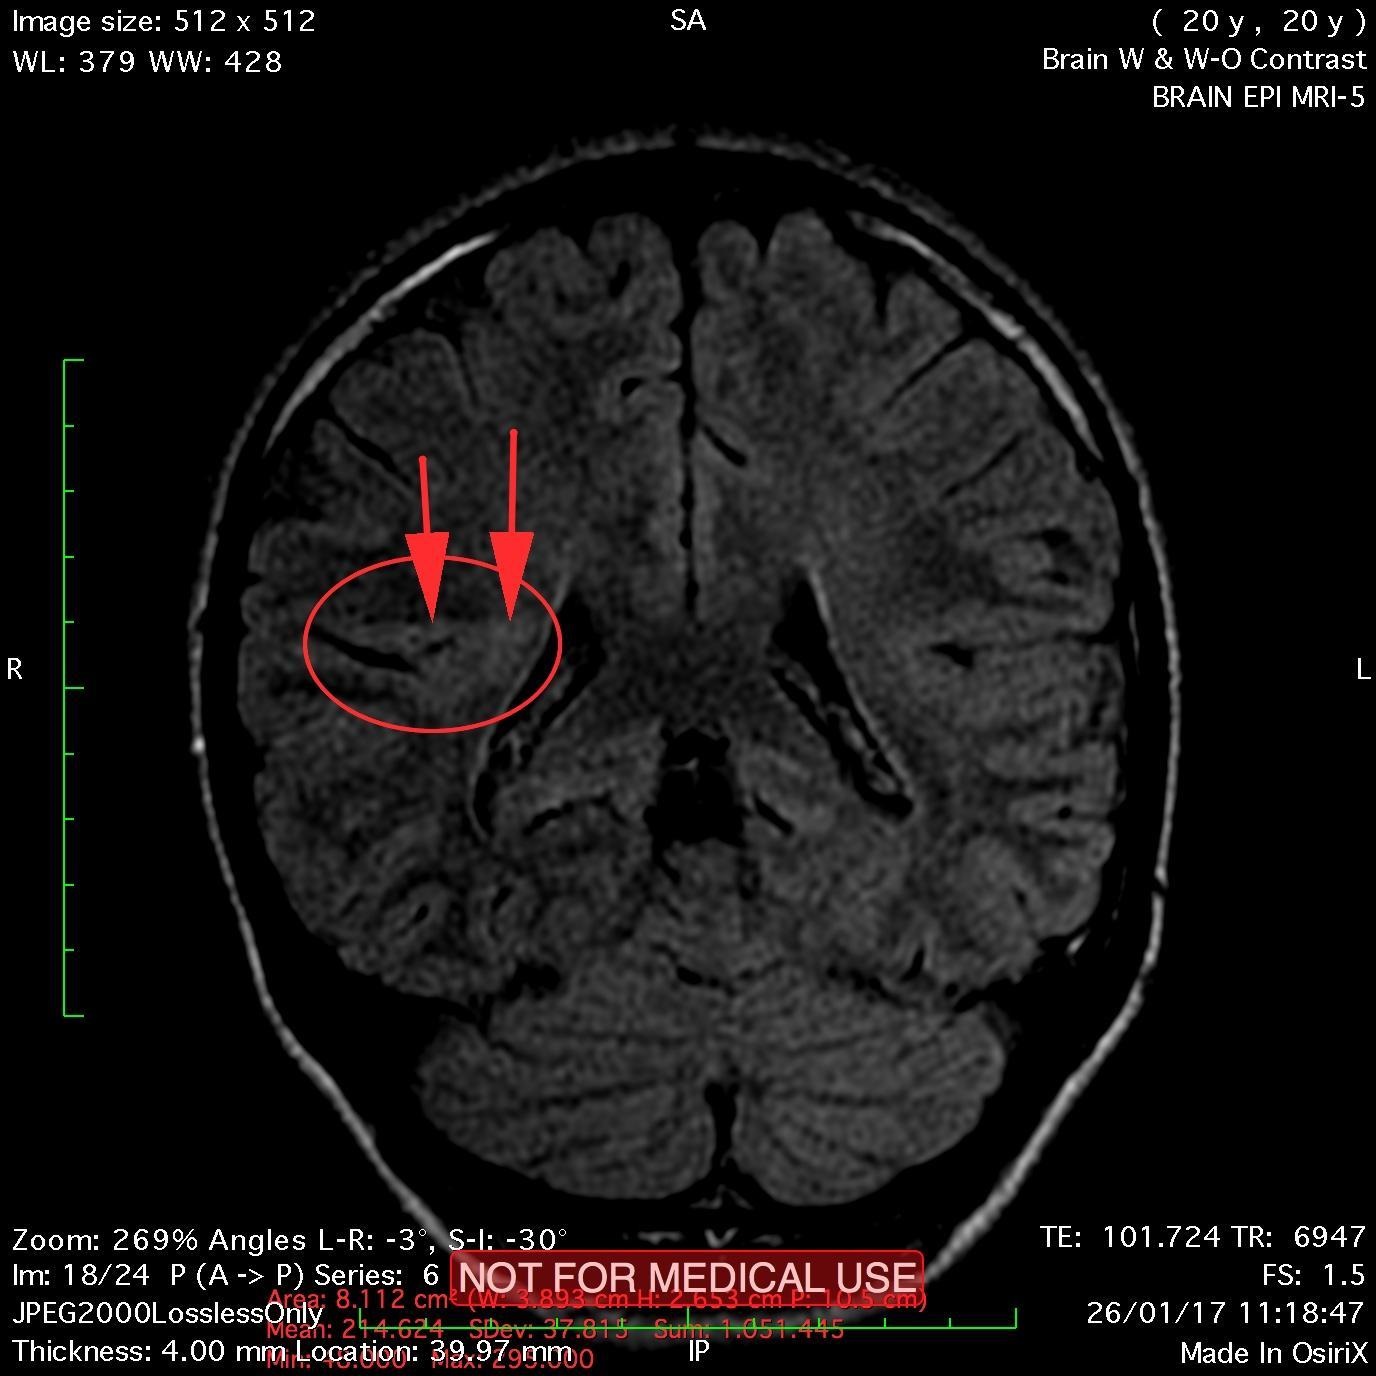

This recent MRI exam WITHOUT Contrast in IHC, revealed a subtle congenital malformation of cortical development within right parietal lobe.

A subtle linear band intensity extending between deep posterosuperior aspect of right Sylvian fissure and posterior aspect of corpus of right lateral ventricle (isointense with gray matter on all sequences). These MRI findings strongly suggest "Type II (Taylor type) focal cortical dysplasia (transmantle cortical dysplasia)" or "transmantle gray matter heterotopia". Virtually, they may be representing two different names for the same entity.